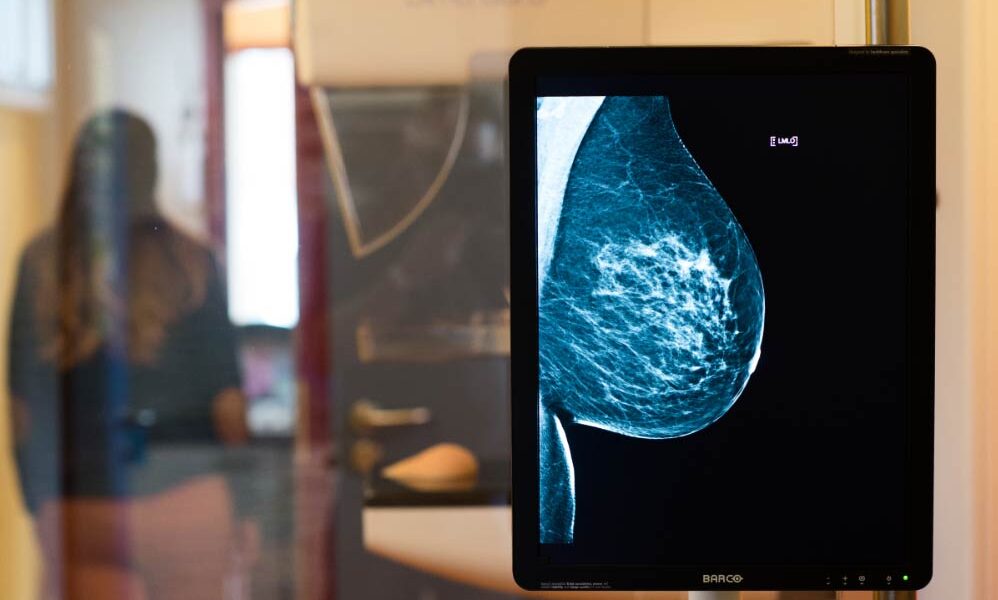

Aún no existen realmente alternativas a la mamografía. Por el momento no pueden ser reemplazadas por ningún otro tipo de procedimiento, dice Weg-Remers, «pero las sonografías y las resonancias magnéticas son importantes para completar la imagen», apunta.

Actualmente también existe la tomografía computarizada de mama, una forma de diagnóstico que está siendo implementada en pacientes desde hace pocos meses, observa Karsten Ridder, un especialista en Radiología que trabaja en la ciudad de Dortmund.

La tomografía computarizada genera imágenes de alta resolución en 3D sometiendo a la persona a una muy baja radiación, explica Ridder, que realiza este tipo de estudios. «Queda claro el contraste del epitelio glandular y las calcificaciones», indica, sin que la mama deba ser «comprimida».

Susanne Weg-Remers también mira con buenos ojos este tipo de estudio. «Como no aplasta la mama, permite determinar con mayor precisión de qué zona sería mejor extraer una muestra», explica. De todos modos, la especialista también advierte que la tomografía computarizada de mama aún está en fase experimental. En Alemania suele ser utilizada en investigaciones y estudios específicos llevados adelante en hospitales universitarios.